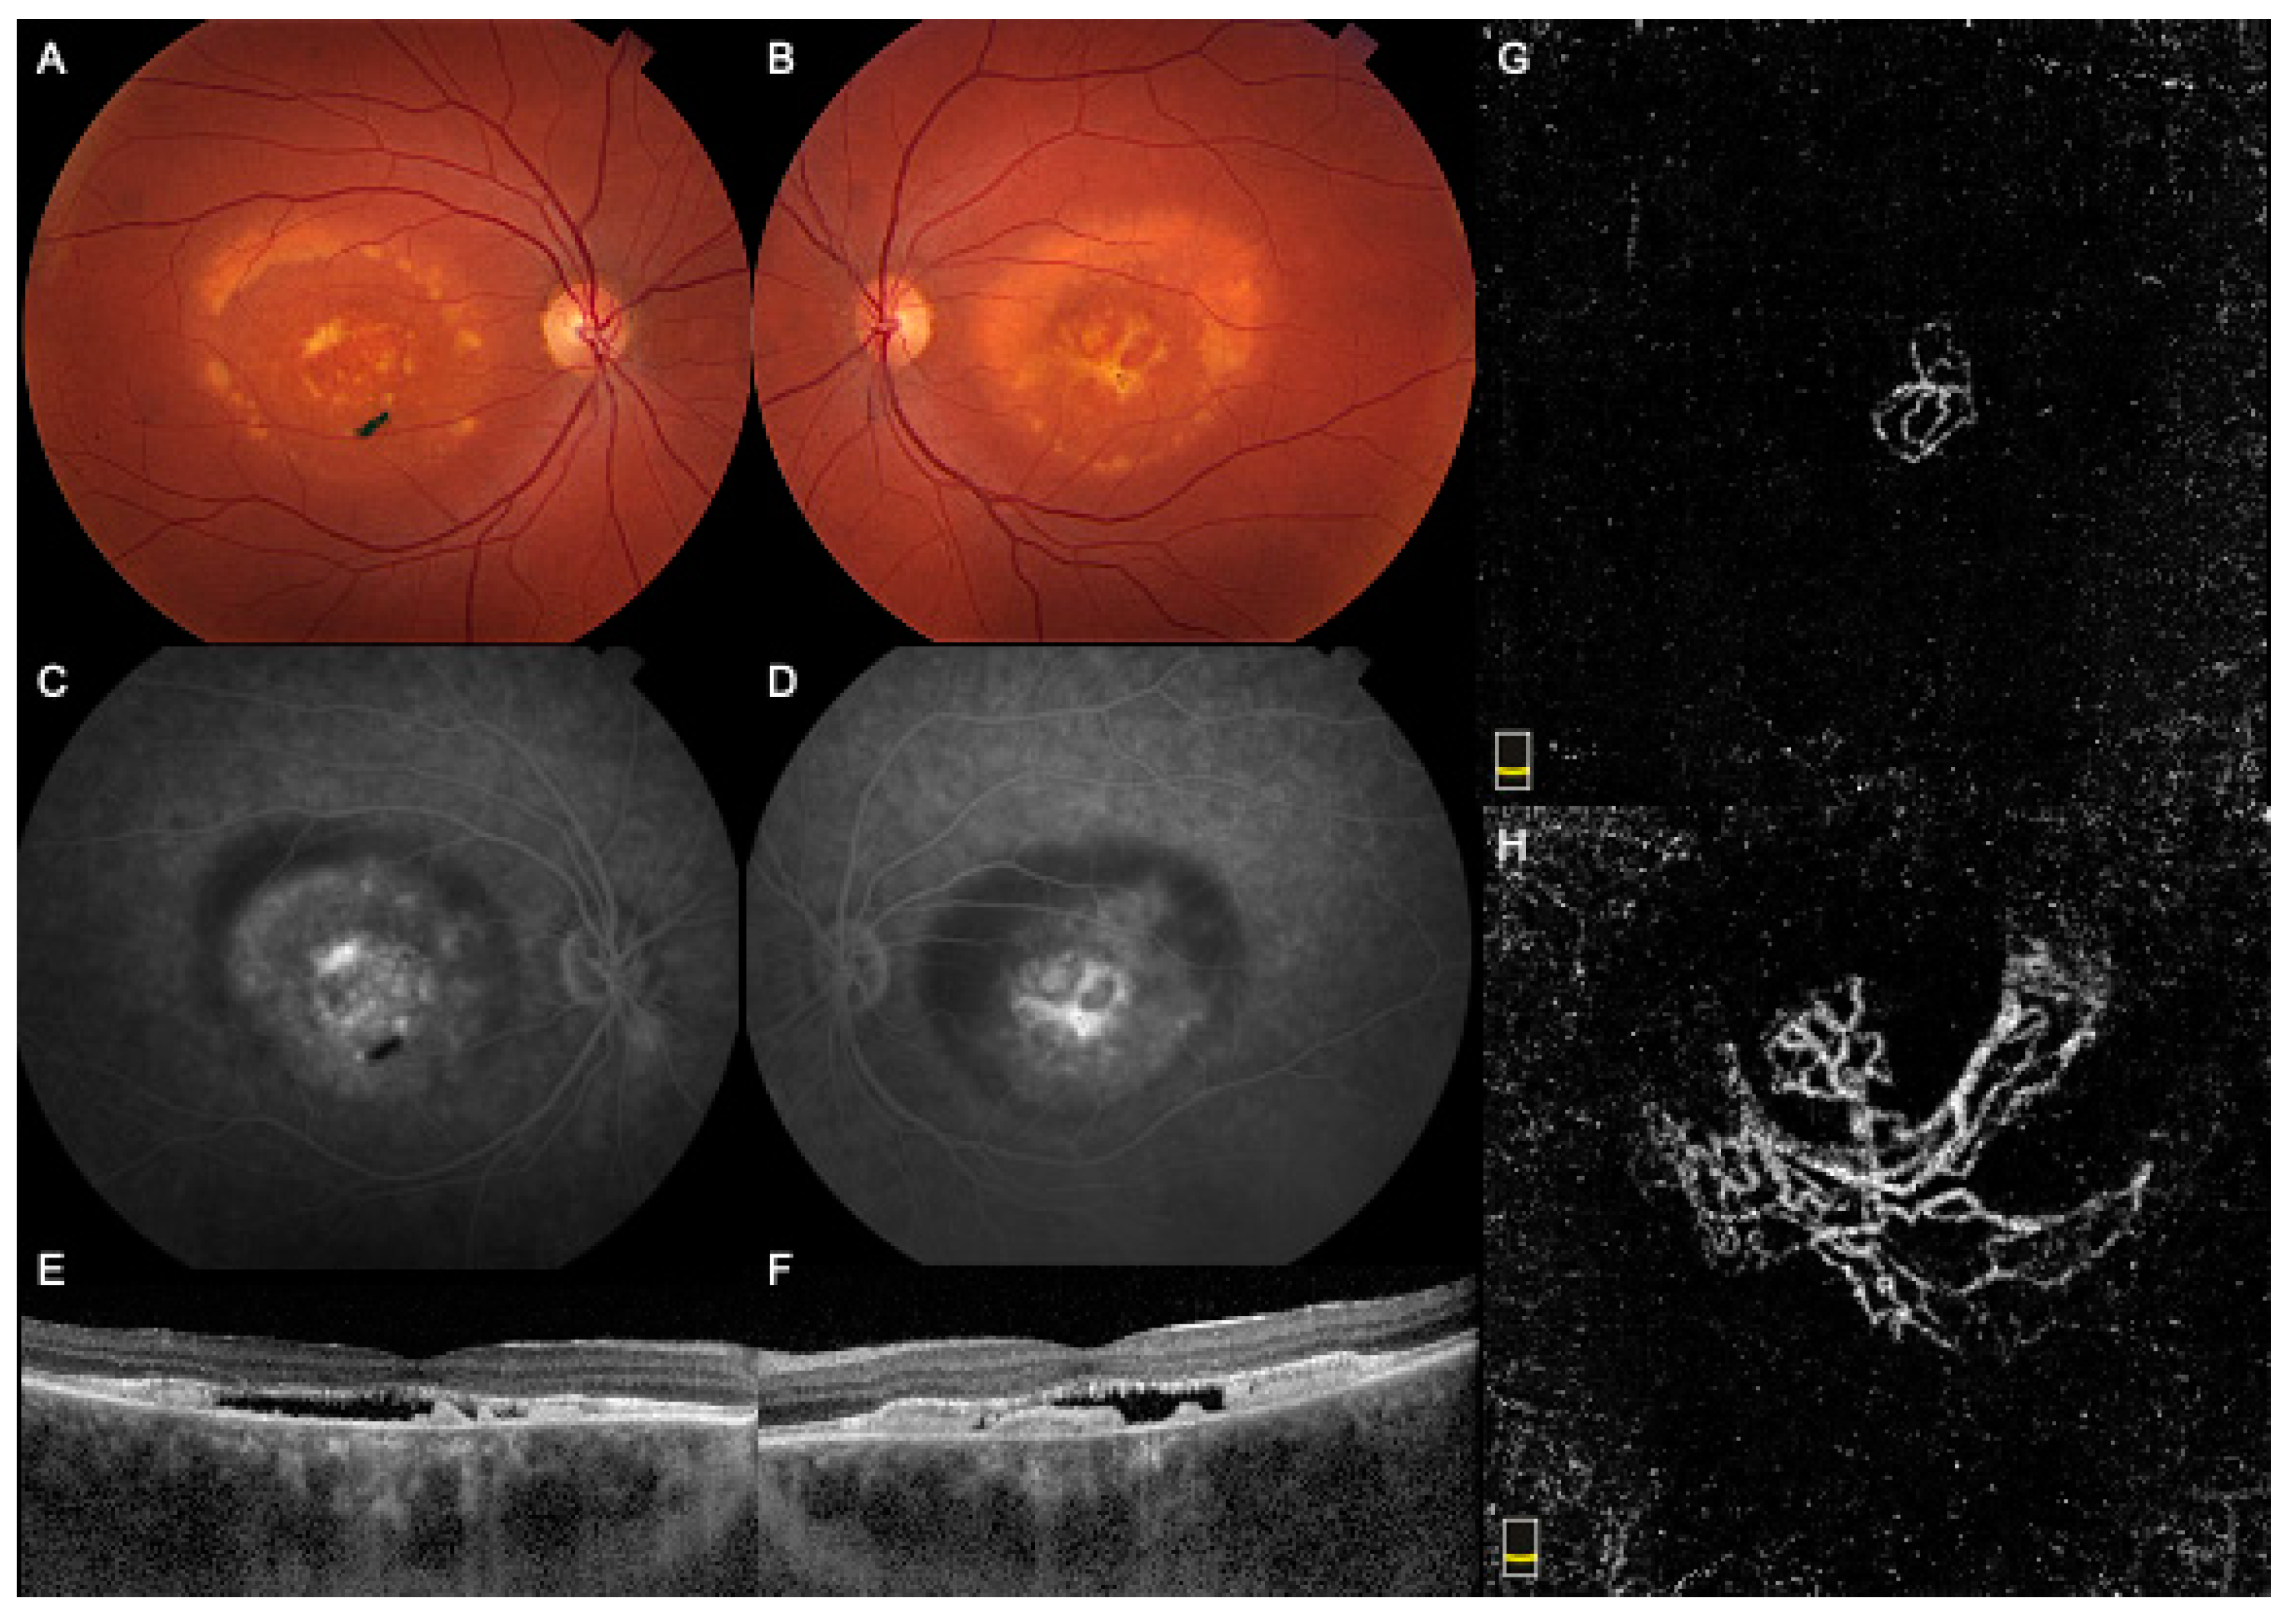

Case 2 was a 34-year-old female who presented complaining of decreasing vision in her RE. The BCVA was 20/40 in the RE and 20/30 in the LE. Multiple family members were diagnosed with BMD, including her father. Fundus examination showed large bilateral vitelliform detachments, subretinal fibrosis, and pigmentary changes (Figure 2A,B). FA showed central dye staining and late pooling within the vitelliform lesions (Figure 2C,D). The SD-OCT demonstrated a shallow subfoveal optically empty space with a hyperreflective RPE detachment in both eyes (Figure 2E,F). B-scan OCTA showed flow pixels within the hyperreflective lesions, while the en-face slab revealed a neovascular network in the outer retinal slabs bilaterally (Figure 2G,H). The patient received two monthly injections of bevacizumab in the RE. Since there was no improvement in vision, subretinal fluid on SD-OCT, or CNV size on OCTA, further intravitreal treatment was deferred with a plan to closely observe for subjective or objective worsening. Her last BCVA was 20/70 in the RE and 20/25 in the LE, with a similar macular appearance on follow-up.

Figure 2. Multimodal imaging of Case 2 showing a choroidal neovascular membrane in both the right eye (RE) and left eye (LE). (A,B). Fundus color picture showing large bilateral vitelliform detachment, subretinal fibrosis, and pigmentary changes. (C,D). Fluorescein angiography showed central dye staining and late pooling within the vitelliform lesions. (E,F). Optical coherence tomography (OCT) demonstrated a shallow subfoveal optically empty space with a hyperreflective retinal pigment epithelium detachment in both eyes. (G,H). En face OCT Angiography revealed a neovascular network in the outer retinal slabs bilaterally. The right, symptomatic eye showed a smaller network with thick caliber vessels that maintained the same size despite treatment. The left, asymptomatic eye showed a large network with large caliber vessels that corresponded to the central fibrotic elements clinically and on the fundus photo.